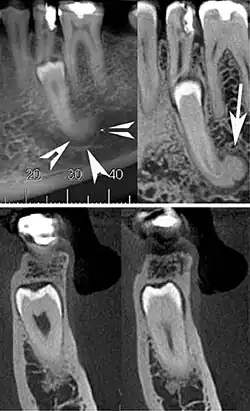

| Cone beam CT images showing a well-defined hyperdense round lesion attached to the root of supernumerary mandibular tooth (arrow head) with a surrounding hypodense rim.[1] | |

Cementoblastoma is slow growing well-defined, radiopaque mass, with a radiolucent peripheral line, that overlies and obliterates the tooth root typically presenting with root resorption. [6] It has a rounded or sunburst appearance. Differential diagnosis include severe hypercementosis, chronic focal sclerosing osteomyelitis, and osteoma.